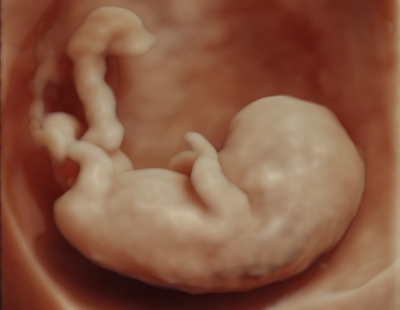

Échographie précoce

Une échographie effectuée en début de grossesse (entre 6 et 11 semaines) sert, en premier lieu, à définir l’âge de la grossesse et son évolutivité. Elle permet également de déterminer la position de la grossesse à l’intérieur de l’utérus ainsi que le nombre d’embryons